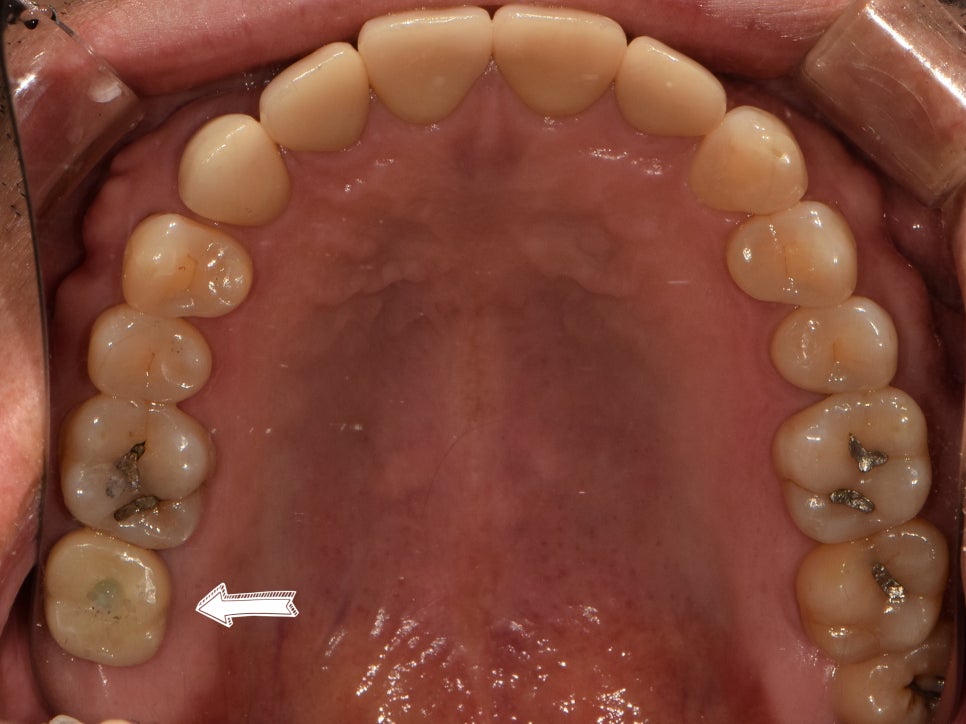

텅 비어있던 곳이 자연스러운 지르코니아로

채워져 있는 것을 볼 수 있습니다.

어금니에 문제가 생겨 불편함이 크셨을 텐데,

성남치과 부작용 없는 임플란트로

건강하고 예쁜 치아를 갖게 되었네요.